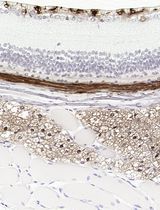

Improved Immunohistochemistry of Mouse Eye Sections Using Davidson's Fixative and Melanin Bleaching

Anne Nathalie Longakit [...] Catherine D. Van Raamsdonk

Nov 20, 2025 1465 Views